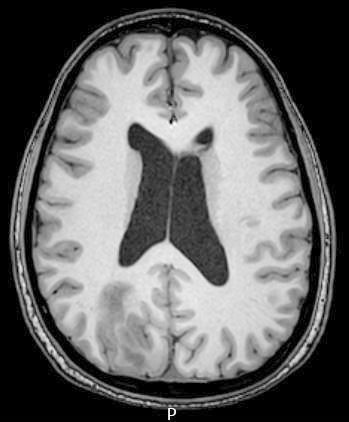

Radiology description

- CT:

- Expanding, intra-axial, poorly defined mass of low density

- Variable calcification may be seen

- Contrast enhancement and central hypodensity due to necrosis, occur with higher grades

- MRI:

- T1 hypodensity and T2 hyperintensity

- T2 hyperintensity with relative FLAIR sequence hypointensity (T2 FLAIR mismatch) is a relatively suggestive indication of IDH mutant astrocytoma (Clin Cancer Res 2017;23:6078)

- Distortion and enlargement of involved areas, including associated cortical ribbon

- Contrast enhancement is typically present in higher grade tumors (J Neurooncol 2019;141:327)

- Ring-like enhancement around central necrosis typical of grade 4

Radiology images